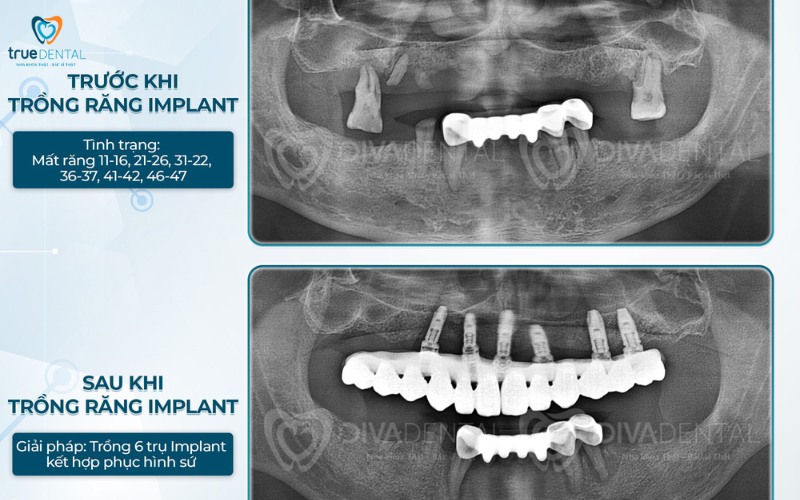

Chụp phim X-quang ConeBeam CT 3D

Đây là bước chẩn đoán quan trọng nhất để biết được cấy ghép implant có ảnh hưởng đến xoang hàm không. Thông qua phim chụp X – Quang bác sĩ sẽ:

- Đánh giá chính xác: Phim X – quang cung cấp hình ảnh chi tiết về cấu trúc xương hàm, đo lường chính xác chiều cao, chiều rộng và mật độ xương còn lại và sàn xoang.

- Lên phác đồ điều trị hiệu quả: Dựa vào phim X – Quang, bác sĩ có thể xác định loại kỹ thuật nâng xoang cần thiết (kín hay hở), vị trí và kích thước chính xác của trụ Implant, từ đó lập kế hoạch trồng răng chi tiết và an toàn nhất, tránh hoàn toàn nguy cơ xâm lấn xoang hàm.